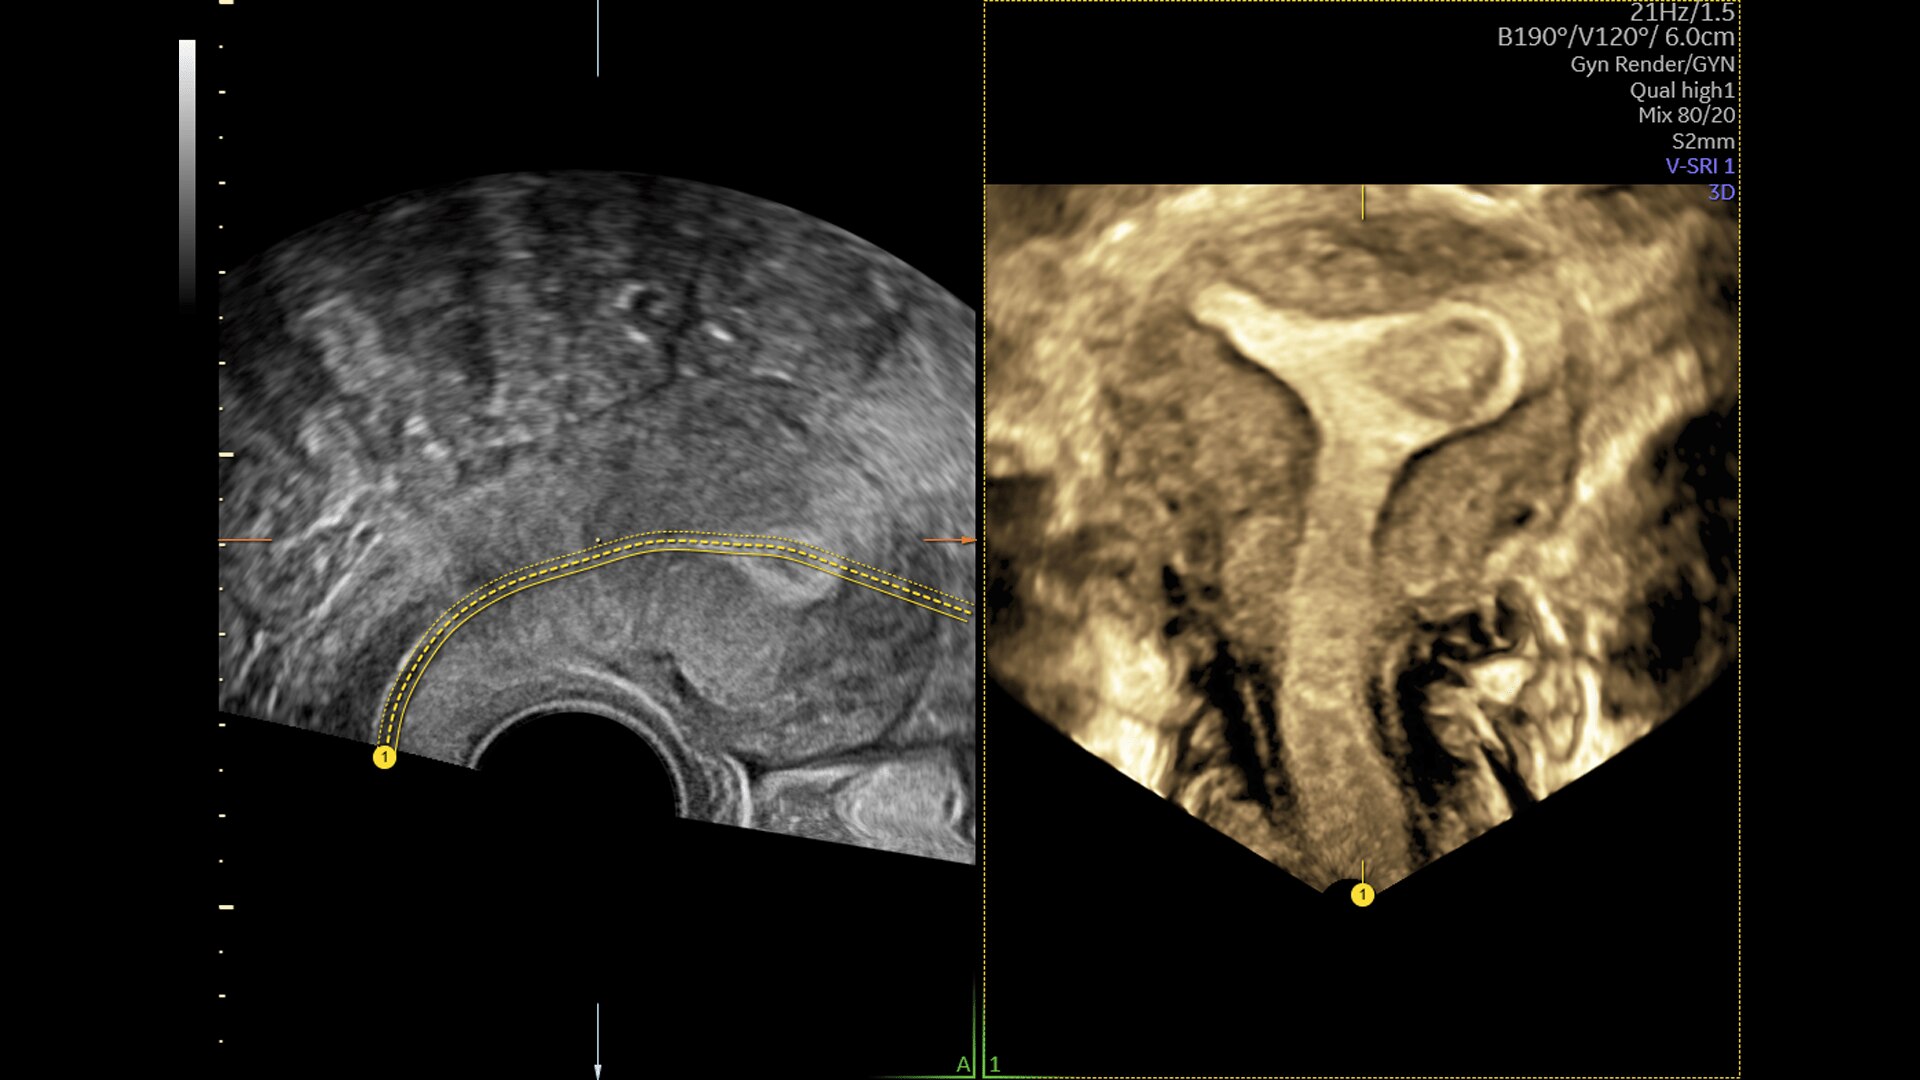

Pelvic Health

Offer patient answers faster with Ai-based automation tools